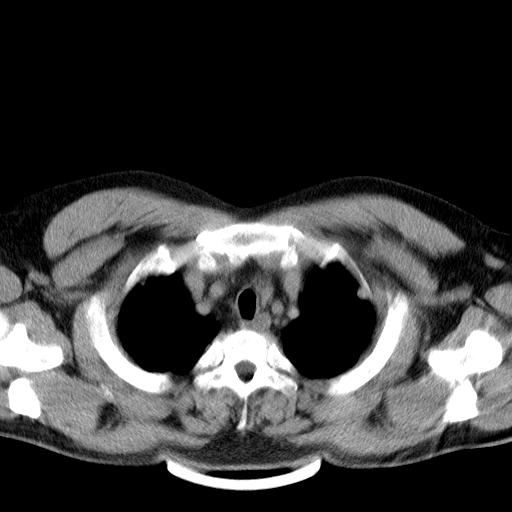

肺内纵隔多发结节,肺内以外周为著,首先考虑转移瘤

纵隔内多发肿大淋巴结,两非弥漫性小结节状病灶,分布范围为肺外围为主,首先考虑为肺内和纵隔内转移性病变。(前不久我科室就遇到一女性38岁,肺癌伴肺内弥漫性转移)

双肺散在多发类圆形结节灶,边缘较光滑,纵隔淋巴结肿大,考虑转移瘤

肺内多发大小不等结节影,以外周为著,纵隔见多个淋巴结肿大;结果病人,35岁,有发烧咳嗽等病史,首先考虑血源性肺脓肿可能性大,建议积极抗炎治疗后复查,除外转移瘤或韦格氏肉芽肿.

两肺多发结节,部分病灶边缘不清,且示毛玻璃影。分布特点为沿血管支气管分布。考虑如下:

1.双肺门及纵隔淋巴结肿大,双肺多发结节,结节病